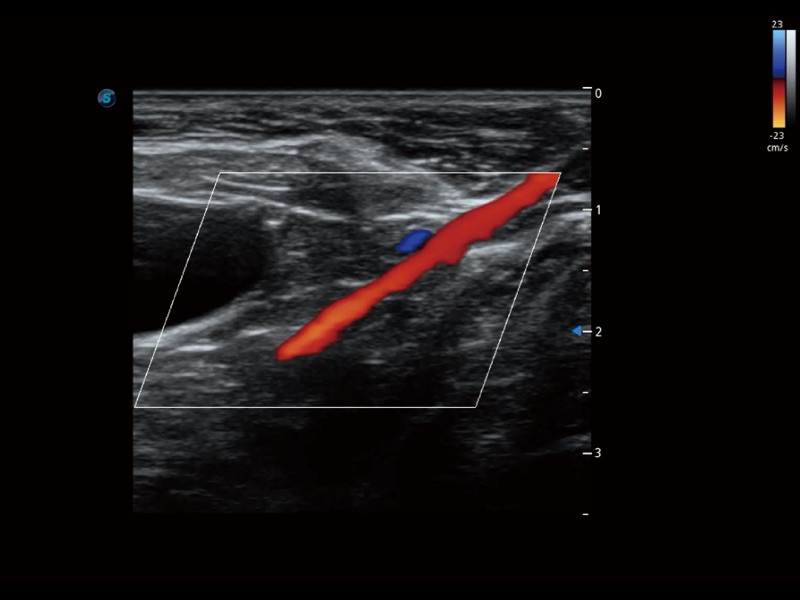

增强穿刺针在动物解剖结构中的位置,提高穿刺介入的安全性和准确性。

通过创新的 Matrix E自适应滤波器和超长时间域算法,极大提升超低速微细血流的检出能力,同时更精准地滤除软组织和噪声信号,为兽用医生提供以往无法通过常规血流获得的疾病诊断信息。

ProPet 70 全新的动物超声智能软件和丰富的探头群,为动物医生提供了高清晰度和精细分辨率的图像,无论在宠物、马科、畜牧还是实验室动物等应用中都可以轻松应对,为您的日常工作带来满意的体验。